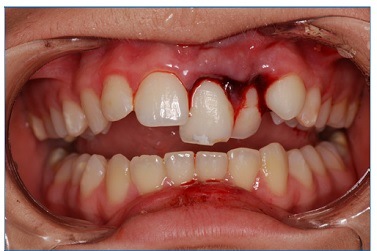

A 15‑year‑old Caucasian female patient was admitted to a private clinic 30 minutes after suffering a severe impact to the oral region during a basketball game at school in 2010. She was not wearing a mouthguard at the moment of the trauma. The intraoral examination revealed a cut on the lower lip and heavy bleeding in the maxilla’s anterior region (Figure 1). Besides, both teeth 21’s (left maxillary central incisor) and 22’s (left maxillary lateral incisor) crowns were slightly dislocated in a palatal and coronal direction, and tooth 21 had an enamel fracture (Figure 2). The patient had vital signs within the normal range and did not have any systemic alterations. Radiographic examination revealed a horizontal root fracture in the middle third of tooth 21 and an enlargement of the periodontal space of tooth 22 (Figure 3). Teeth 21 and 22 did not respond to the cold test with Endo Ice (Maquira, Maringa/PR, Brazil), while the response from teeth 12 (right maxillary lateral incisor), 11 (right maxillary central incisor), and 23 (left maxillary canine) was compatible with a normal pulp. The patient reported pain during the percussion exam on all teeth involved.

Figure 1 Clinical aspects at the emergency care: intense bleeding in the anterior region of the maxilla involving teeth 11, 12, 21, 22, and 23